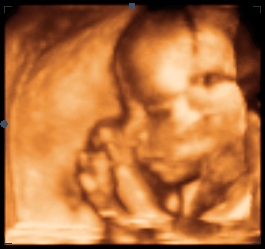

3D приказ на лицето на бебето